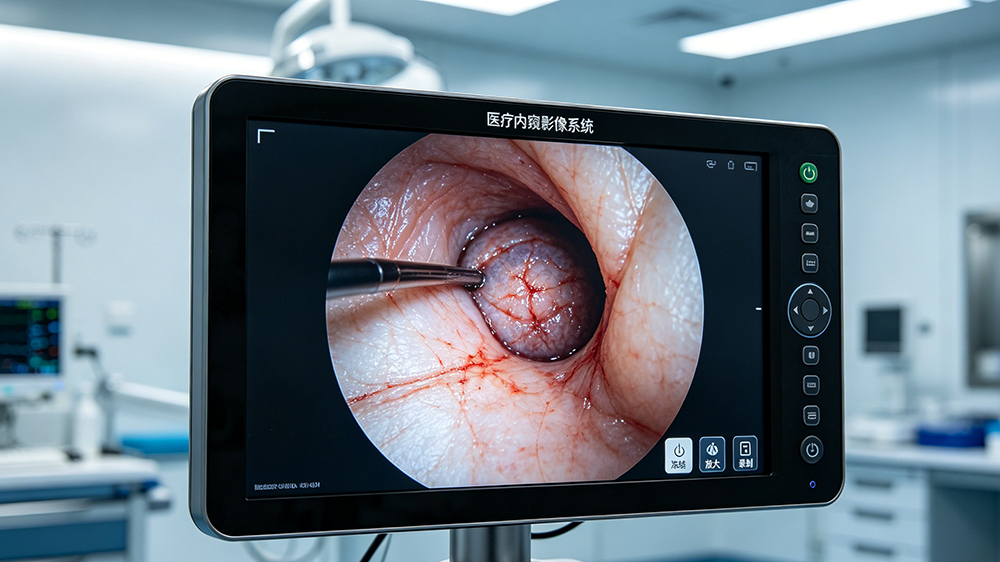

医疗内窥行业触摸显示器Gamma值与色域可调解决方案

医疗显示器:为生命精准呈现,为临床安全护航